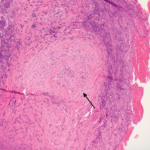

Granulomatosis with polyangiitis (GPA) is a type of anti-neutrophil cytoplasmic antibody (ANCA) associated small vessel vasculitis that typically affects the kidneys, lungs and sinuses.1 Due to an overlap in signs and symptoms, GPA may initially be difficult to distinguish from IgG4-related disease, another condition that can affect multiple tissues and has variable presentations. Further complicating…

Based on the classification system developed by the Chapel Hill Consensus Conference, anti-neutrophil cytoplasmic antibody (ANCA) associated vasculitis is defined as a necrotizing vasculitis involving small vessels that is associated with myeloperoxidase (MPO) ANCA or proteinase 3 (PR3) ANCA and displays minimal immune deposits. The mechanism behind the pathogenesis of ANCA-associated vasculitis is not fully…

Granulomatosis with polyangiitis (GPA) was first described in the British Medical Journal in 1897 by Scottish otolaryngologist Peter McBride.1 GPA is a relatively rare, systemic necrotizing vasculitis that can make diagnosis challenging. The incidence has been estimated anywhere between two and 12 cases per million.2 GPA mainly affects adults between the ages of 45 and…